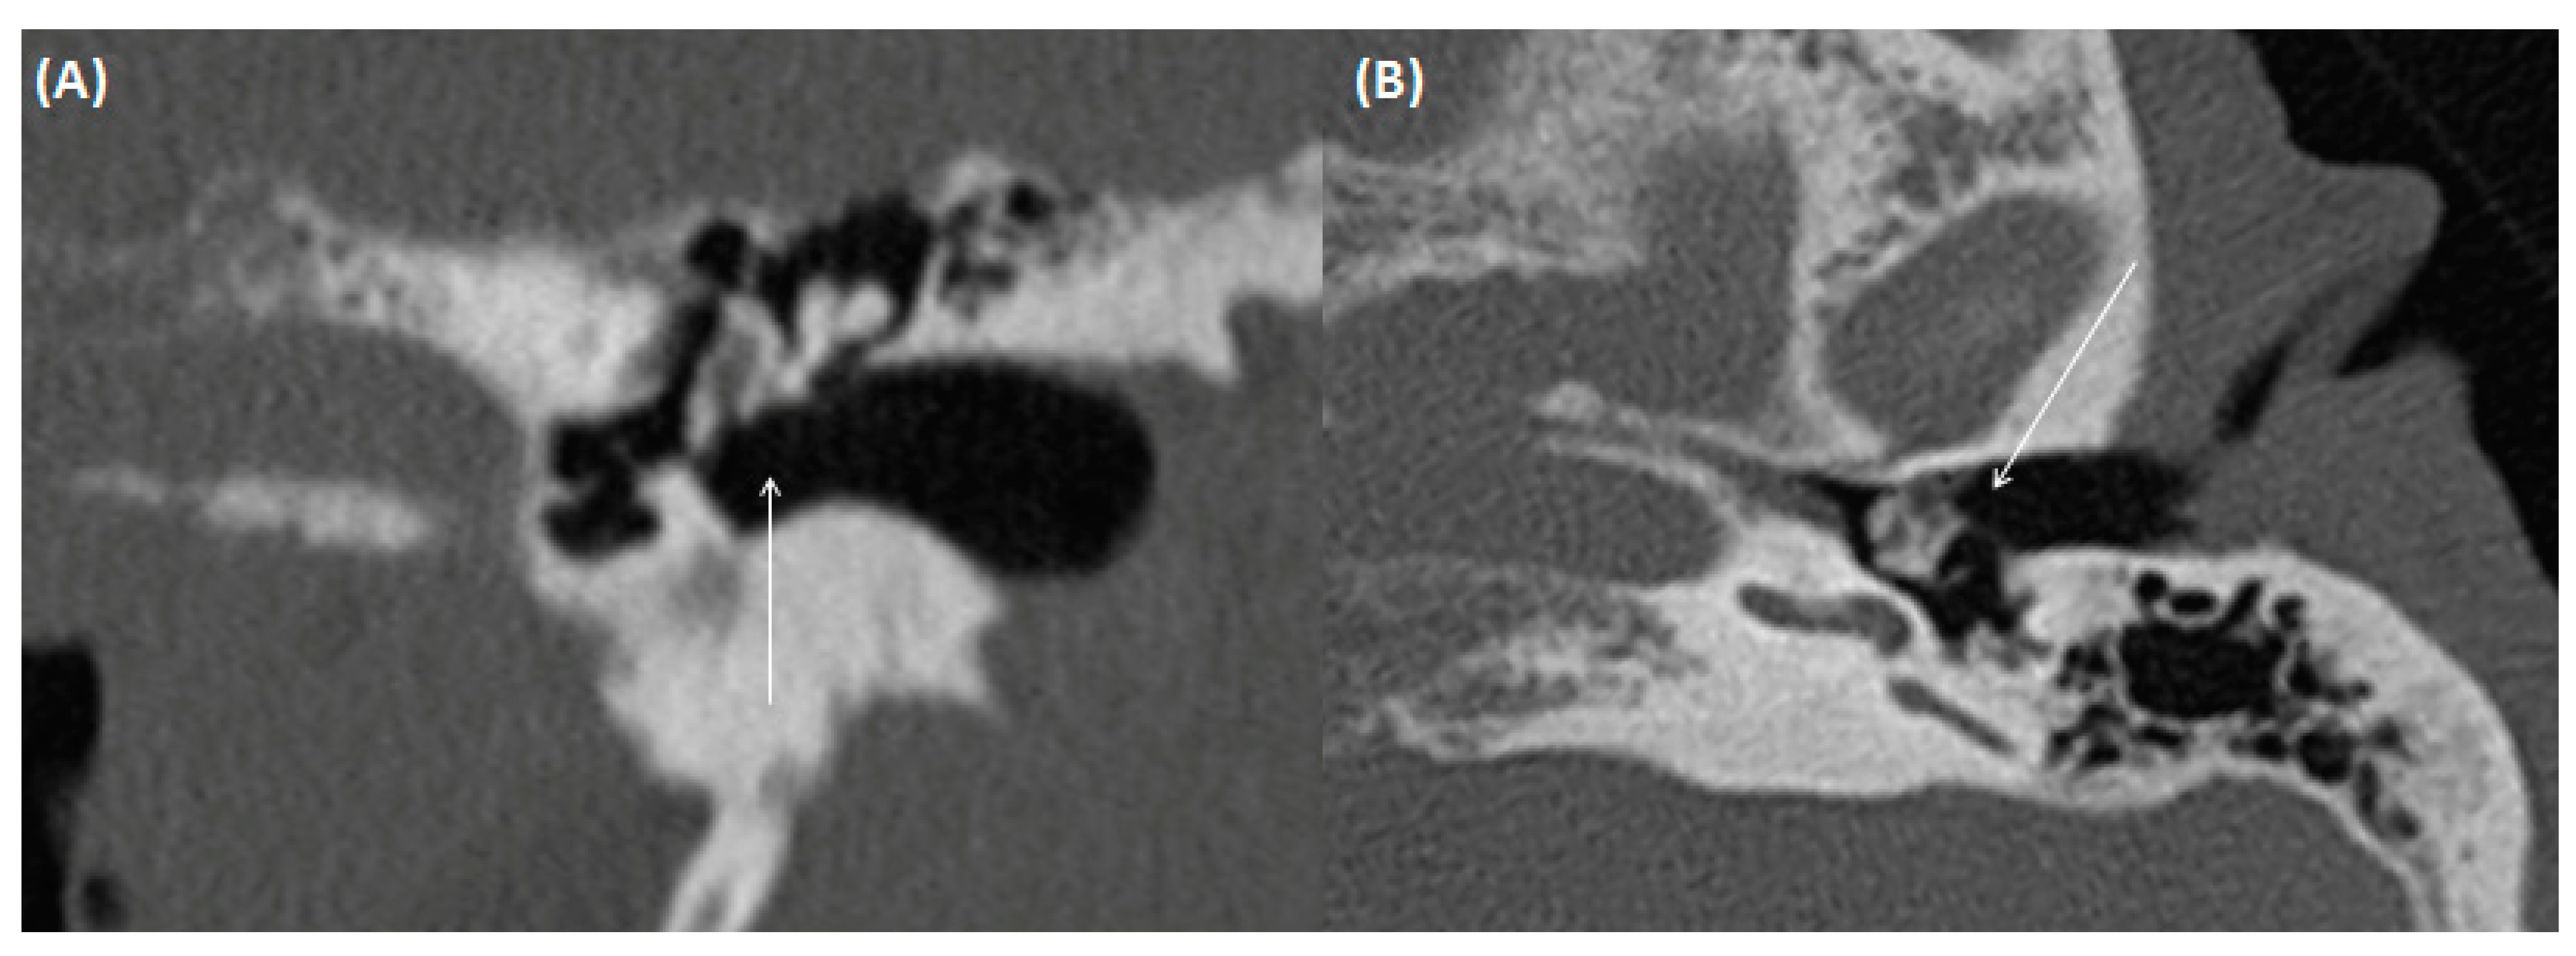

3.1.2. Cholesteatoma of the External Ear Canal

3.1.3. Auditory Canal Exostosis